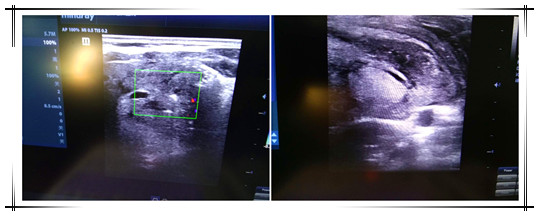

患者林某某、福州仓山籍、男性、34岁,以发现右颈部肿物1月余为主诉入院,甲状腺彩超示:右侧中下部探及一偏低回声团,大小约3.88cm x 2.54cm。经过术前周密检查,决定实施低温等离子消融术切除甲状腺肿瘤。消融治疗时间很短,约30分钟,术后病人即可下地行走、起居自如,第二天便可出院,患者林先生自己都不敢相信小小一根针可以获得如此惊人的效果。